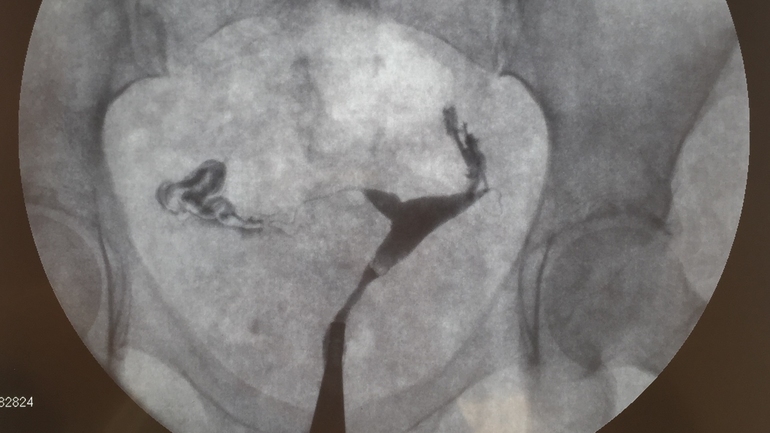

Результат: обе трубы проходимы, у правой вообще все хорошо, а левая извита и подтянута спайками за матку. В заключении доктор сказал, что лапара не помешает, но в целом можно пока не торопиться, месяца 3-4 попытаться забеременеть и с одной.

Кстати, что важно: во время процедуры доктор разглядел маленькое углубление в матке, сделал отдельный снимок этой ямки, сказал похоже на миоматозный узелок под вопросом, но делать с этим пока ничего не надо, если беременность наступит - то этот момент сам подлечится.